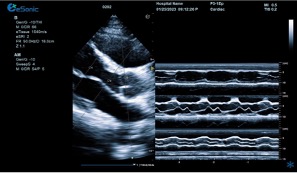

临床病例(一)

女性,68岁,临床诊断:冠心病

超声表现:左房大,左室壁运动幅度明显减低,以室间隔较明显;心包腔内见无回声区,右室前壁8mm,左室侧壁10mm。

冠心病、心包积液